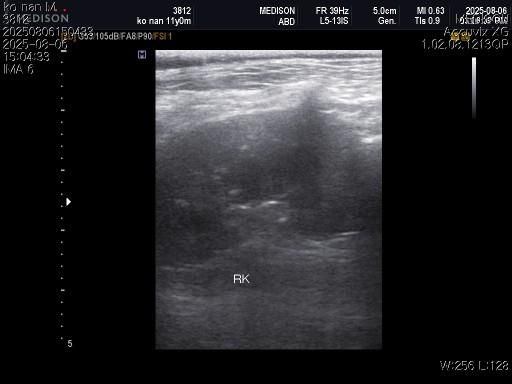

1) 혈액검사와 엑스레이 그리고 초음파상 혈뇨의 원인이 나타나지가 않는지 궁금합니다.

3) 신장결석이 어느정도인지도 궁금합니다.

4) 양쪽 부신의 크기가 궁금합니다.